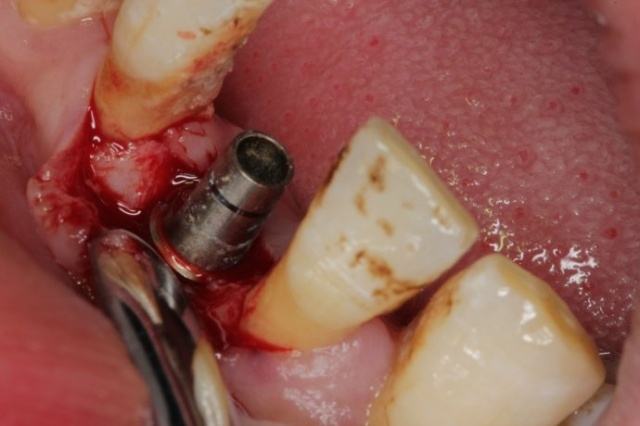

術(shù)中:

因?yàn)槭中g(shù)的時(shí)候因?yàn)榇蛄寺樗帲谑中g(shù)后爸爸也說沒有疼痛感,所以整個(gè)手術(shù)過程都比較輕松,也許是因?yàn)樽隽耸中g(shù),爸爸告訴醫(yī)生說有些不適應(yīng),醫(yī)生說是正常的情況,在麻藥勁之后還會(huì)有疼痛感,然后告訴我們需要注意的各種事項(xiàng),之后就回家了。